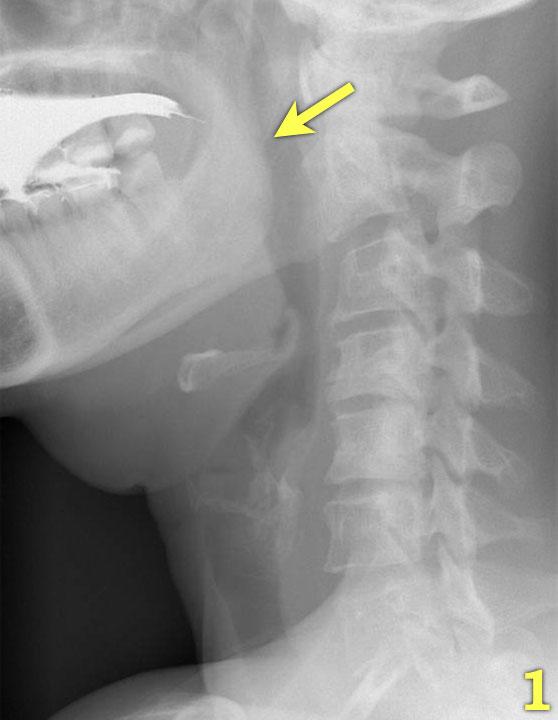

- Nền lưỡi và vòm miệng mềm đóng khoang miệng ở phía sau (mũi tên) để ngăn thức ăn tràn vào hầu họng và thanh quản đang mở.

- Lưỡi bắt đầu vận chuyển thức ăn về phía hầu họng (mũi tên vàng).

Thanh quản vẫn còn mở và ở vị trí bình thường (mũi tên xanh lá). - Vòm miệng mềm nâng lên để ngăn thức ăn tràn vào vòm mũi họng (mũi tên xanh lá) và lưỡi đẩy thức ăn tiếp tục ra phía sau (mũi tên vàng).

- Xương móng nâng lên và thanh quản đóng lại (mũi tên xanh lá). Lưỡi đẩy thức ăn xuống dưới trong khi cơ khít thực quản trên co lại.